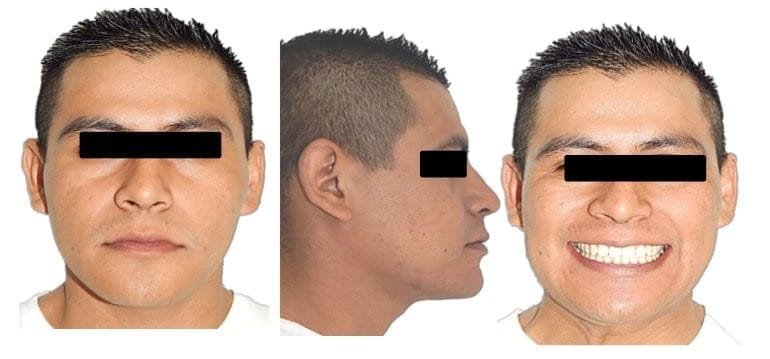

Análisis extraoral

Se observa en las fotografías de frente, cara larga con un mentón desviado hacia la derecha. Tanto en reposo como en sonrisa, en la de perfil una notable proyección del mentón respecto al maxilar y en la frontal se evidencia la poca proyección de la zona malar y tercio medio de la cara. (Figs. 1, A-C)

Fig.1 Fotografías extraorales de Inicio. A) Frente. B) Sonrisa. C) Perfil.